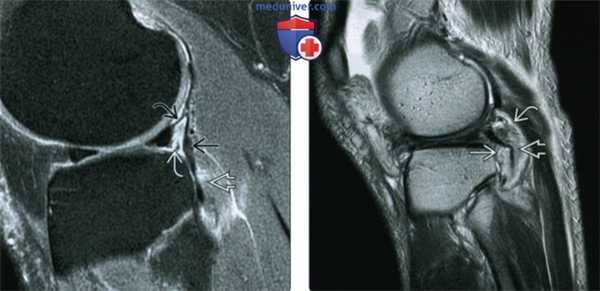

(Слева) На рисунке заднего среза заднебоковою угла показан разрыв подколенной мышцы и латерального края дугообразной связки. Подколенное отверстие располагается проксимальнее.

(Справа) МРТ Т2ВИ, режим подавления сигнала от жира, коронарный срез: у пациента с острым разрывом передней крестообразной связки определяется разрыв подколенного сухожилия и латерального пучка дугообразной связки. Отдельные связочные структуры задне-бокового угла могут не визуализироваться сразу после травмы тяжелой степени. (Слева) На рисунке аксиального среза заднебокового угла показано подколенное сухожилие, проходящее через подколенное отверстие. Также показаны дугообразная связка, фабелломалоберцовая связка, сухожилие двуглавой мышцы бедра (ДМБ) ТЕЗ и малоберцовая коллатеральная связка (МБКС).

(Справа) MPT PDBИ, режим подавления сигнала от жира, аксиальный срез: у пациента с травмой заднебоковою угла легкой степени определяется подколенное сухожилие, латеральный пучок дугообразной связки, фабелломалоберцовая связка, ДМБ и МБКС.

(Слева) MPT PDBИ, режим подавления сигнала от жира, сагиттальный срез: определяется травма подколенного сухожильно-мышечного сочленения легкой степени. Дугообразная связка не повреждена. Отмечается разрыв передненижней подколенно-менисковой фасцикулы, но задневерхняя фасцикула не повреждена.

(Справа) MPT Т2ВИ, сагиттальный срез: определяется частичный разрыв подколенного сухожильно-мышечного сочленения тяжелой степени. ПМБС и дугообразная связка разорваны.